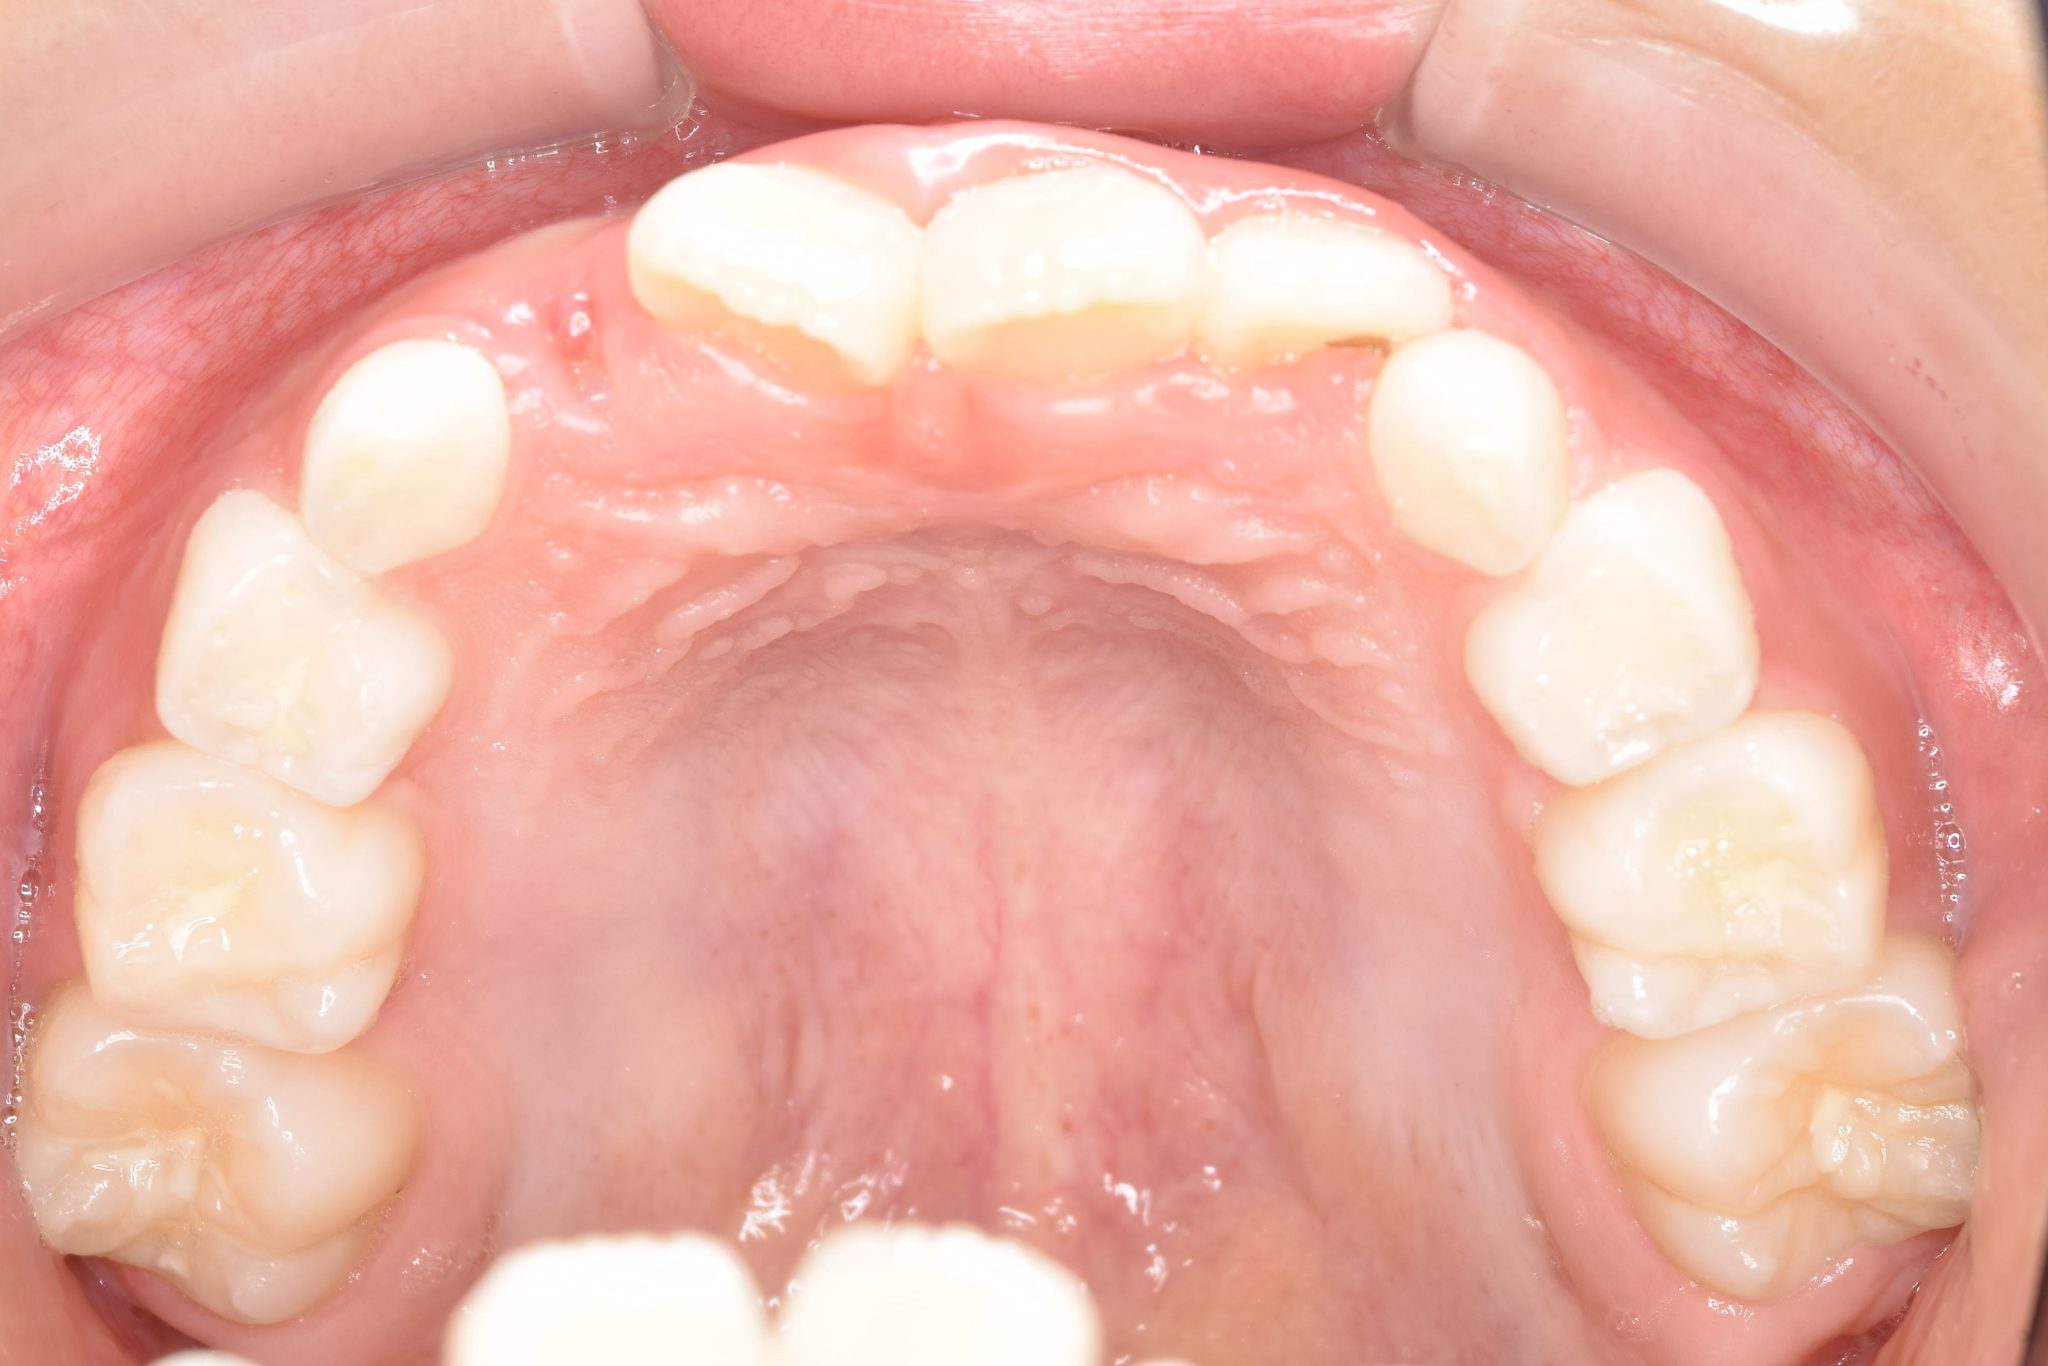

ビフォー

主訴 受け口

施術内容 上顎急速拡大装置と下顎リンガルアーチを用いて上下顎骨を拡大した。

上顎前方牽引装置を用いて上顎骨を前方に成長促進させた。

その後マウスピース型矯正装置で歯牙を配列し良好な咬合を獲得した。

治癒期間 2年9ヶ月間